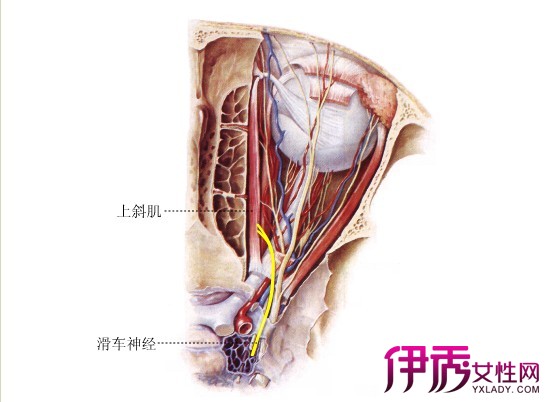

滑车神经

【图】滑车神经属于哪个神经 教你识别外展神经损伤的鉴别诊断

神经解剖外传——简单又不简单的滑车神经

神经解剖外传——简单又不简单的滑车神经

视神经的外侧,然后在上直肌的下方越至眼眶的内侧前行,终于滑车上动脉